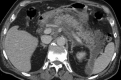

Abdominal CT showing acute non-lithiasic edematous pancreatitis. Note the diffuse enlargement of the pancreas, thickening of peripancreatic fat, and the presence of fluid collections, including a large peri-splenic one. No intra-glandular necrosis or hemorrhagic areas were appreciated